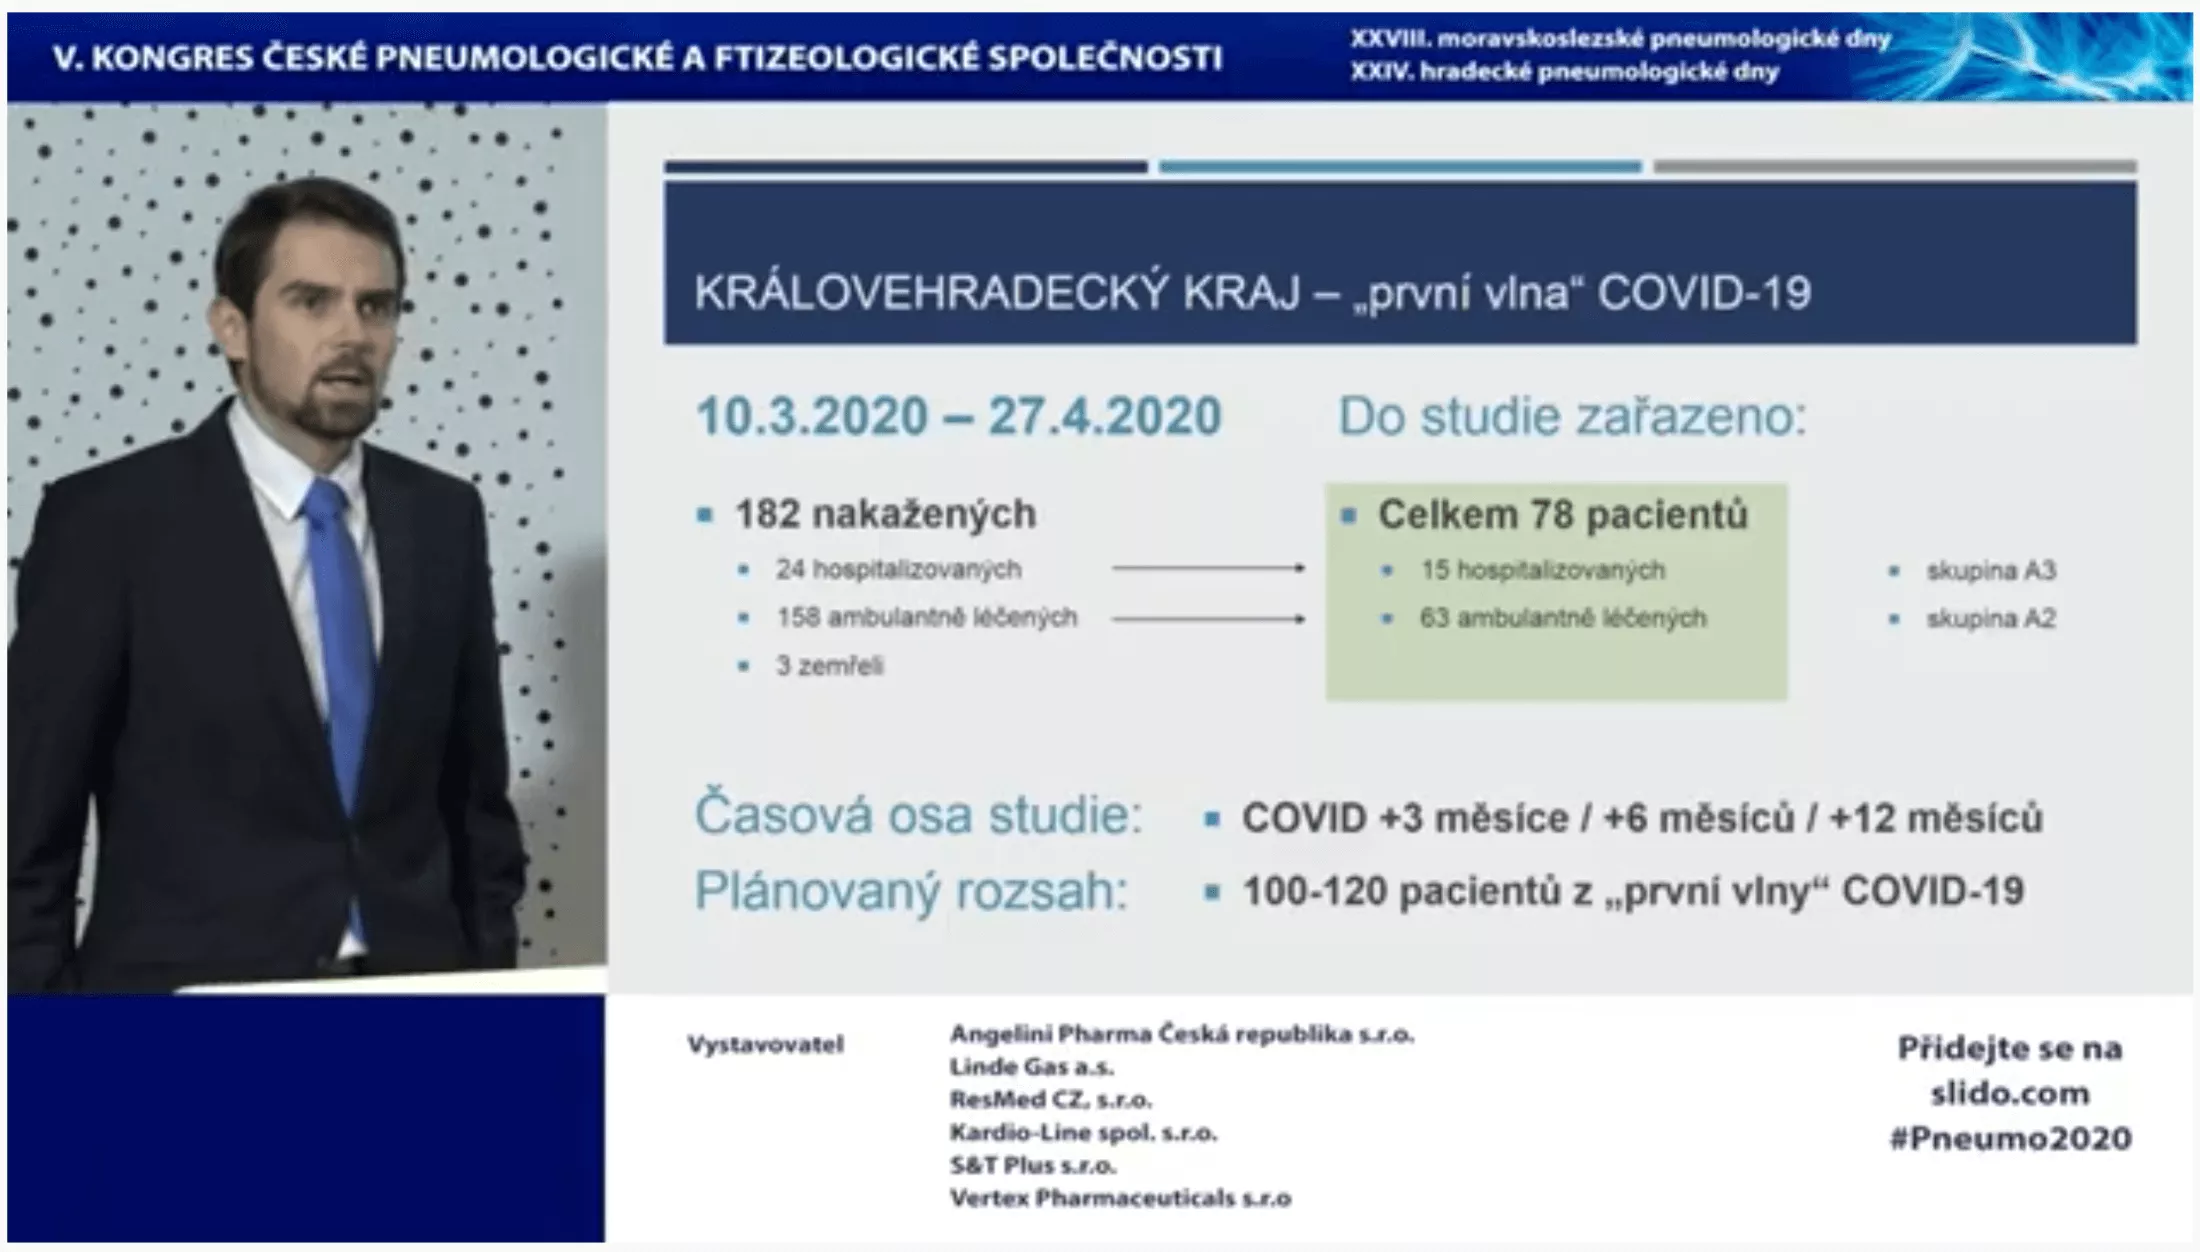

Ve FN Hradec Králové v současnosti probíhá komplexní multioborová prospektivní studie sledující následky u pacientů po prodělaném onemocnění COVID-19. Do studie jsou zváni všichni nemocní v Královéhradeckém kraji, kteří byli v „první vlně“ koronavirové pandemie, konkrétně v období od 10. 3. do 27. 4. 2020, pozitivně testováni na SARS-CoV-2 metodou PCR a jsou starší než 18 let. Navzdory tomu, že Královéhradecký kraj patřil v jarní vlně pandemie k regionům s nejnižším počtem COVID-19 pozitivních osob (celkem jich bylo 182 – z toho 24 hospitalizovaných, 158 ambulantně léčených a 3 nemocní zemřeli), do studie se podařilo zařadit již 78 pacientů (skupina A2 – 15 osob po prodělané hospitalizaci, skupina A3 – 63 osob léčených ambulantně). Celkem mají investigátoři v plánu do studie zařadit 100–120 nemocných z „první vlny“ COVID-19. Časový plán počítá s tím, že její účastníci budou systematicky sledováni po 3, 6 a 12 měsících od onemocnění COVID-19.